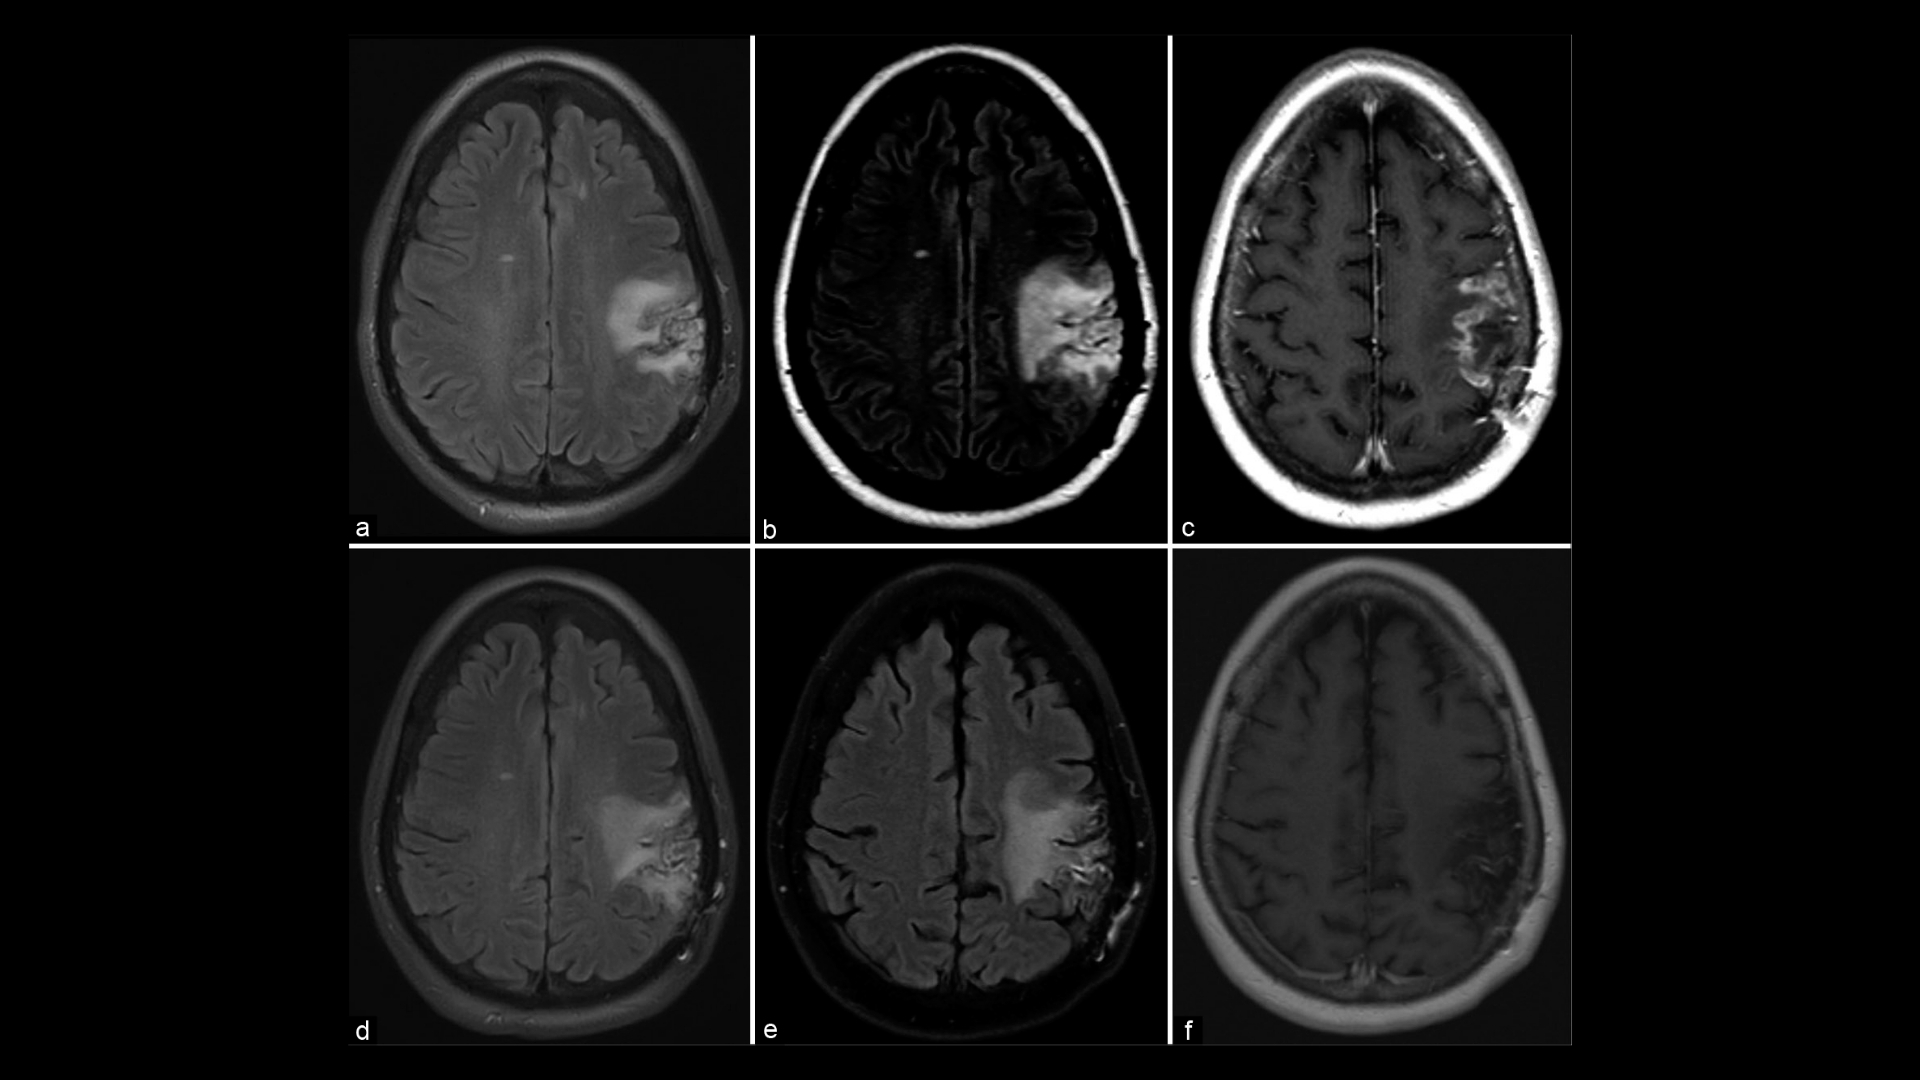

第 1 期的特徵是局部病變,僅限於中樞神經系統的單一區域,通常可透過詳細的影像模式 (如 MRI) 早期偵測出來。

特性: 多個腫瘤病灶或病灶大小輕微增加 (2-4 公分),MRI/CT 掃描顯示輕微的顱內壓影響。

準確診斷 原發性 CNS 淋巴瘤 淋巴瘤的治療涉及多種先進的方法,每種方法在有效的治療規劃中都扮演著重要的角色。影像技術的使用,例如 MRI 或 PET-CT 掃描,對於找出淋巴瘤的確切位置和範圍至關重要。MRI 掃描可提供腦部和脊髓的詳細影像,讓專家能夠高精確度地偵測腫瘤。